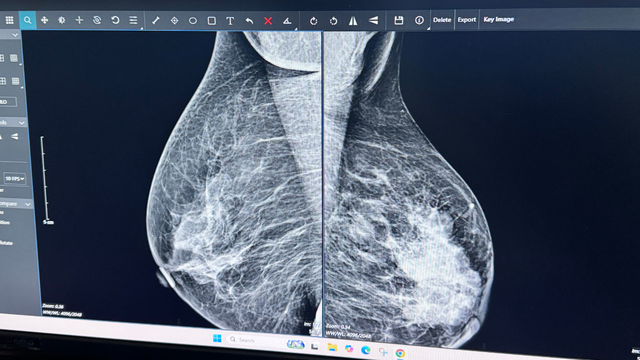

Bác sĩ Trang khuyến nghị, phụ nữ nên siêu âm hoặc chụp X-quang tuyến vú định kỳ, đặc biệt khi có dấu hiệu bất thường. Đây là cách đơn giản nhưng hiệu quả để phát hiện sớm, tránh những tiếc nuối muộn màng.